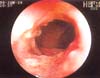

Se realizó nueva colonoscopia en la que se observaron lesiones ulcerosas irregulares:

Múltiples, de 2 a 3 cm de diámetro, con fondo recubierto de fibrina entre áreas respetadas de mucosa normal en colon transverso, descendente y sigmoide. En el ciego, se observó una extensa lesión de iguales características que rodeaba la válvula ileocecal (figura 1), obstruyéndola parcialmente; la progresión del colonoscopio al íleon mostró compromiso similar en los últimos diez cm del íleon distal (figura 2), que adoptó una morfología tubular. Se tomaron múltiples biopsias en las que se observó un epitelio colónico ulcerado (figura 3) con áreas aisladas de necrosis (figura 4) que mostraron la presencia de gran cantidad de microconidias (figura 5) y que fueron confirmadas como correspondientes a HC.

Figura 1. Compromiso del ciego y de la válvula íleocecal, observándose una extensa lesión ulcerada de bordes irregulares y fondo fibrinoide que obstruye parcialmente la luz de la válvula ileal